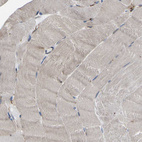

Immunohistochemical staining of human Cerebral cortex shows moderate cytoplasmic positivity in neuronal cells.